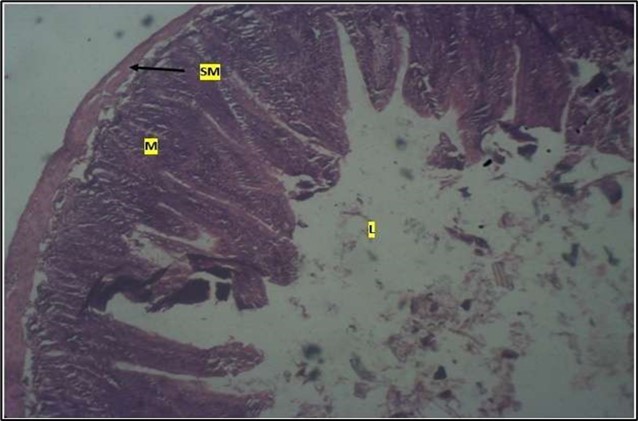

Micrographs of The Small Intestine

Histological examination of the small intestine result in control animals revealed a normal architecture with the red pulp and white pulp with no pathological observation Figure 2. Administration of Abelmoschus esculentus at low dose shows an increased cellularity with numerous cells in the Mucosa and the villi projecting towards the lumen. Focal metaplasia of mucosal cells alongside villous disruption was also observed (Figure 3). The high dose group showed normal cellular architecture with no villous disruption (Figure 4).

Figure 2.Control showing the mucosa with intestinal villi (v) projecting towards the lumen (l) and the underlying smooth muscle layer (sm) all appearing normal

Figure 3.Low dose showing numerous epithelial cells in the mucosa (m) with villi projecting towards the lumen (l). The is focal metaplasia of the mucosal cells with villous disruption. smooth muscle layer appears normal. H & E. X40